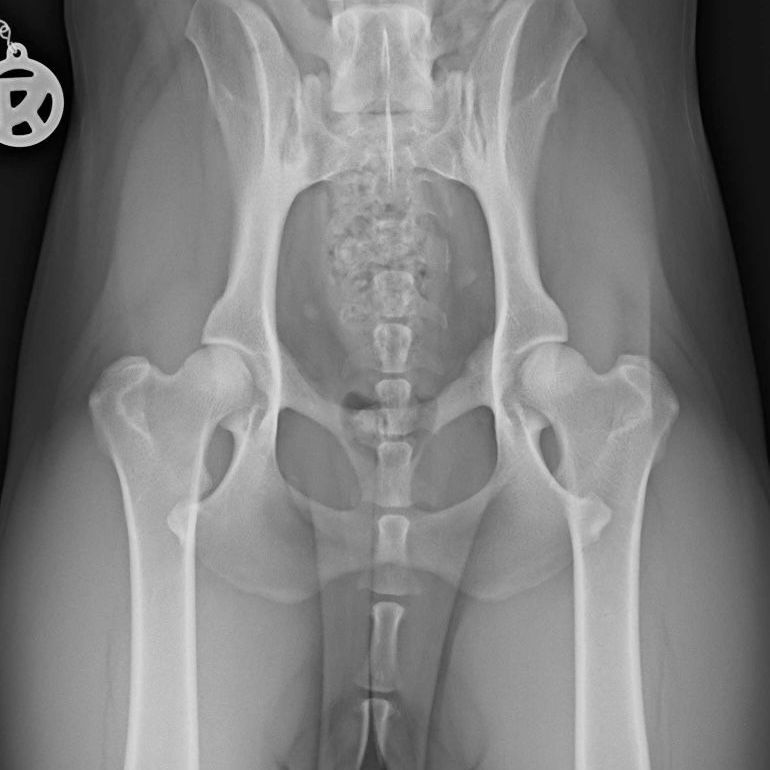

Ein Bandscheibenvorfall beim Hund tritt auf, wenn der gelartige Kern einer Bandscheibe aus dem Faserring austritt, das Rückenmark komprimiert oder sogar verletzt und/ oder auf umgebenden Nerven drückt.

- Rasse: bestimmte Rassen wie Dackel, Französische Bulldogge und Pudel sind aufgrund ihrer langen Rücken und kurzen Beine (Chondrodystrophie) anfälliger für Bandscheibenvorfälle.